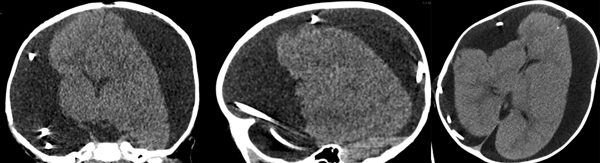

En las siguientes 2 semanas la paciente presentó cefalea de manera progresiva más deterioro del nivel de conciencia y vómitos, por lo que se indicó TC y radiografía de control, en estas se observó el catéter de derivación dentro del espacio subdural en su totalidad debido a migración cefálica completa (Figuras 1 a 3).

Figura 2. Tomografía computarizada en vistas axial, coronal y sagital. Se observa el sistema intracraneal.